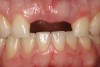

The Ca(OH)2 regimen for No. 8 continued for about a year when the patient, now age 11, presented with a horizontal fracture about 2.5 mm apical to the CEJ. No further endodontic treatment of No. 8 was attempted beyond the four previous Ca(OH)2 treatments. The coronal portion of No. 8 was retained for about 4 years before it was removed at age 15 (Figure 5 through Figure 7). Over that 4-year period, Ca(OH)2 in the canal was expended and not replaced.

Fig 5. Age 15. Facial view of the developing ridge after removal of coronal segment of tooth No. 8.

Figure 5